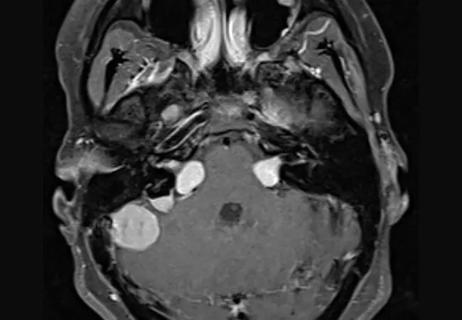

22-NEU-2892117_vestibular-schwannomas-meningiomas_650x450

May 5, 2022/Cancer

Large Series Finds Monitoring Acceptable for Most Meningiomas in Patients With Neurofibromatosis Type 2

Younger patients and those with peritumoral brain edema warrant closer follow-up, earlier treatment